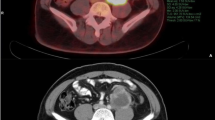

Examples of how ROIs were drawn in CT, PET-CT, and MRI are described in Fig. 1. In case 1, the median value of the mean CT value, SUVmax, and mean ADC value were -94 HU, 1.97, and 0.55 × 10–3 mm2/s, respectively.

Examples of how the ROIs were drawn in CT, PET-CT, MRI, and pathological specimens: hematoxylin–eosin 100 × magnification. Case 1: A 73-year-old man with WDLS. On CT, the tumor has a very low density, similar to that of normal fat tissue. The ADC map showed an uneven tumor with very low signal intensity and a slightly hazy border. Case 2: A 70-year-old man with WDLS. This large tumor was uneven and showed slightly high density on CT. The ADC map showed a very high signal intensity. The tumor was well circumscribed. Case 3: A 40-year-old woman with DDLS. Most of the tumors consisted of WDLS. A small area with very high density was found in a large well-differentiated tumor on CT. In this area, the ADC value was low on the ADC map, and the SUVmax was very high on PET-CT. The boundary was unclear on ADCmap, and the ROI on ADC map was drawn with reference to the area of SUVmax. Case 4: A 77-year-old man with DDLS. A well-circumscribed and uneven tumor was imaged and showed high density on CT and low signal intensity on ADC map. PET-CT showed a very high SUVmax